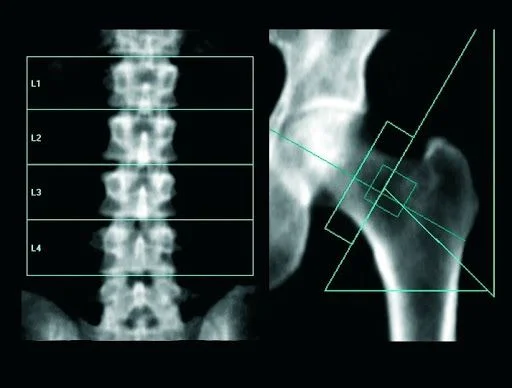

Injúria Renal Aguda (revisão Lancet 2025)